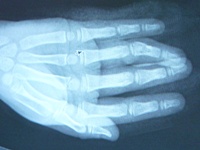

Lucas Before webUpon arrival, it was determined that Lucas didn’t have a pulse in his finger, possibly due to injury to the arteries. Surgery was performed around 4 p.m., and it was following that procedure the Neuschwanders first heard the word “reattachment.”

“Even after the surgery, the doctors couldn’t detect a pulse in the finger. That’s when we were told Lucas needed reattachment surgery because there wasn’t blood flow to his finger,” says Lori. “We were stunned. His finger wasn’t severed, it was still attached, but because it wasn’t getting blood flow, he was in danger of losing it.”

Dr. Goldfarb repaired the blood vessels in Lucas’ finger to reestablish blood flow around 9 p.m., close to 12 hours following the initial trauma.

“Dr. Goldfarb told us that it’s best to perform these surgeries within six to eight hours of the injury, and it was then that we realized how close Lucas came to losing a finger,” says Lori.